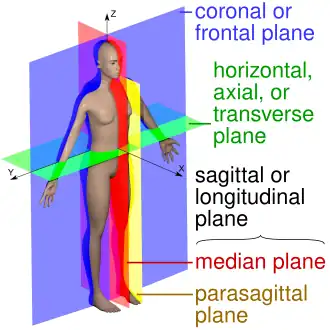

The main anatomical planes of the human body, including mid-sagittal or median (red), parasagittal (yellow), frontal or coronal plane (blue) and transverse or axial plane (green) | |

The sagittal plane (/ˈsædʒɪtəl/; also known as the longitudinal plane) is an anatomical plane that divides the body into right and left sections.[1] It is perpendicular to the transverse and coronal planes. The plane may be in the center of the body and divide it into two equal parts (mid-sagittal), or away from the midline and divide it into unequal parts (para-sagittal).

- The terms median plane or mid-sagittal plane are sometimes used to describe the sagittal plane running through the midline. This plane cuts the body into halves (assuming bilateral symmetry),[3] passing through midline structures such as the navel and spine. It is one of the planes which, combined with the umbilical plane, defines the four quadrants of the human abdomen.[4]

- The term parasagittal is used to describe any plane parallel or adjacent to a given sagittal plane.[5] Specific named parasagittal planes include: